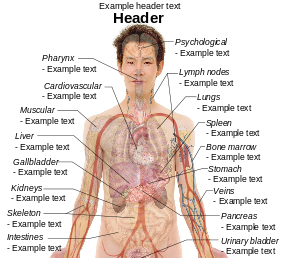

File:Tuberculosis symptoms.svg

| DescriptionTuberculosis symptoms.svg |

English: Main symptoms of different variants and stages of tuberculosis (See Wikipedia:Tuberculosis), with many symptoms overlapping with other variants, while others are more (but not entirely) specific for certain variants. Multiple variants may be present simultaneously.

Human body diagramsMain article at: Human body diagrams Template location: Template:Human body diagrams How to derive an imageDerive directly from raster image with organsThe raster (.png format) images below have most commonly used organs already included, and text and lines can be added in almost any graphics editor. This is the easiest method, but does not leave any room for customizing what organs are shown.

Adding text and lines: Derive "from scratch"By this method, body diagrams can be derived by pasting organs into one of the "plain" body images shown below. This method requires a graphics editor that can handle transparent images, in order to avoid white squares around the organs when pasting onto the body image. Pictures of organs are found on the project's main page. These were originally adapted to fit the male shadow/silhouette.

Organs:

Derive by vector templateThe Vector templates below can be used to derive images with, for example, Inkscape. This is the method with the greatest potential. See Human body diagrams/Inkscape tutorial for a basic description in how to do this.

Examples of derived worksMore examples